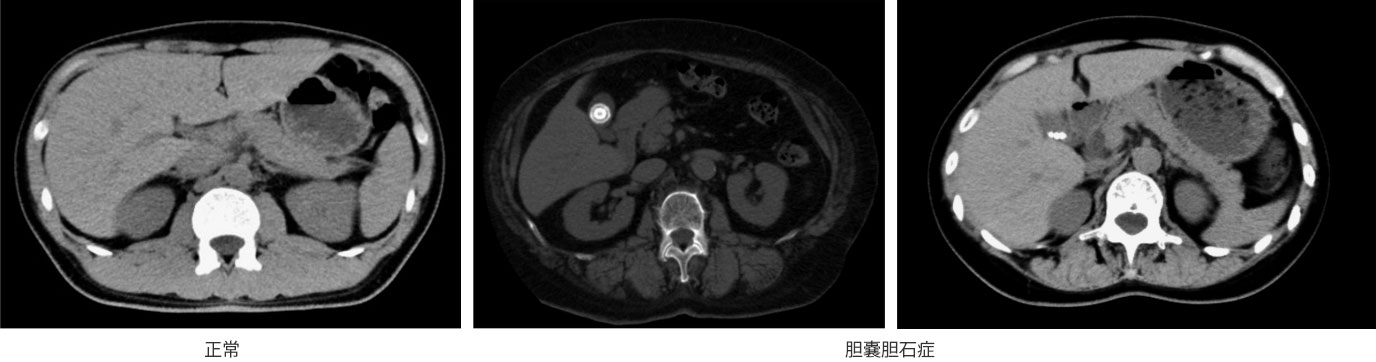

消化酵素を溜めている袋(胆のう)の中に何らかの原因でできた石を胆石と呼び、胆嚢の中に石があることを胆のう結石といいます。検診などで見つかることも多く、無症状の場合には経過を観察することもありますが、石が胆管に詰まると胆のう結石症を発症します。その症状は、みぞおちの右側を中心とした激しい痛みが典型的で、右肩や背中の痛みを伴う場合もあります。血液検査や腹部CT検査などで診断し治療方針を決めていきます。